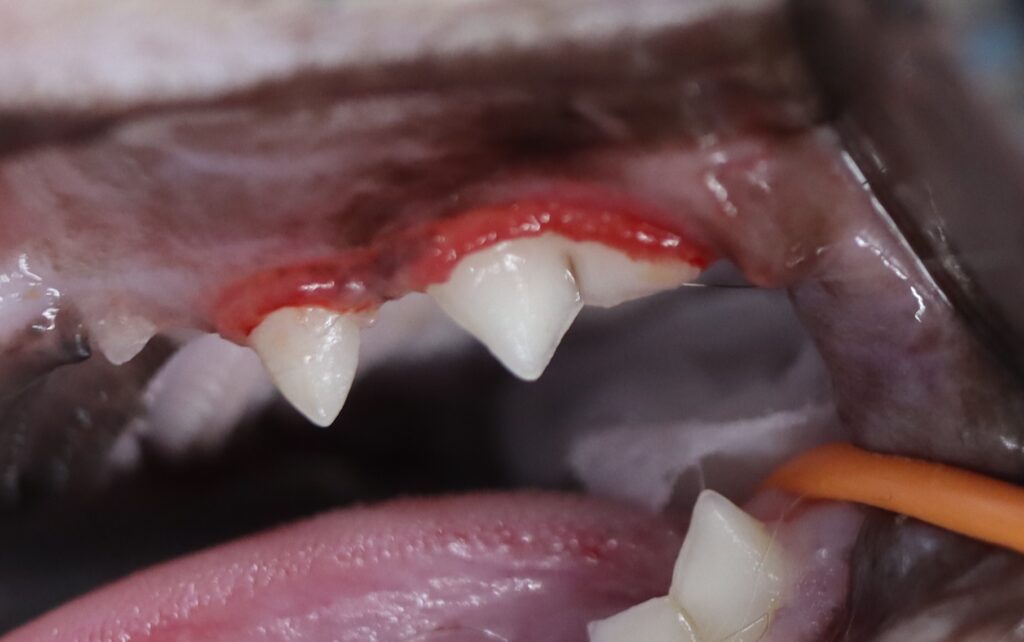

上顎大臼歯に歯石沈着と歯肉の発赤が認められました。

- 診断:軽度歯周病(歯科レントゲンで軽度の歯槽骨吸収を確認)、

- 治療:全身麻酔下でのスケーリングとルートプレーニング、遊離歯肉の切除